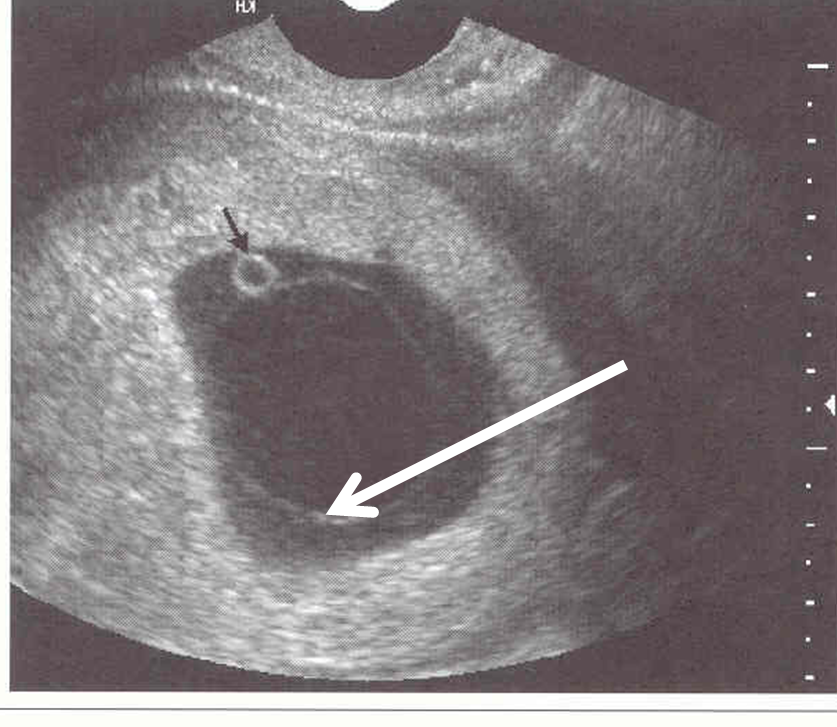

NOT BLACK ARROW

dark ring around gest sac

choronic cavity

darkest circle

amniotic cavity

thin white curved line at top

amniotic membraine

1 – decidua capsularis

2- Chorionic membrane

3 – amniotic cavity

4 – chorionic cavity

5- yolk sac

6 – decidua basalis

Double decidual sac sign

Typically seen around 7 weeks